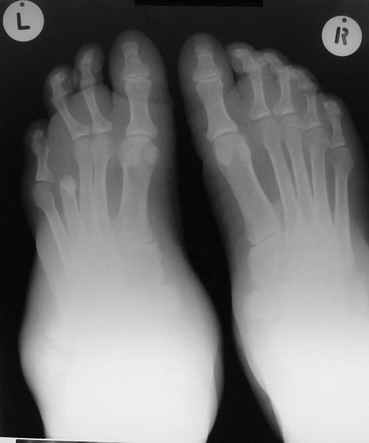

Уажаемые коллеги,представленные рентгенограмммы я показывал на нашем х-рей митинге - они были встречены с большим интересом.. Ну, ещё бы - я сам эту патологии встречал раза три за всю свою долгую жизнь:

После меня выступал с новыми находками для своей коллекции Эмануэл Лакью Тесема, хирург-ортопед из Эфиопии: Мне понравились его находки:

Кто шустрый - при какой патологии встречается так называемые "суставы Шарко"?Второе приобретение доктора Эмануэла мне понравилось своим романтическим названием: Candle bone - <кость-в-виде-оплывающей-свечи> : Просто редкая патология:

VR> Кто шустрый - при какой патологии встречается так называемые <суставы Шарко>?

Сирингомиелия,

Травма спинного мозга

Опухоль

Т.н. нейрогенная артропатия бвает при диабете, периферических нейропатиях, заболеваниях спинного мозга... Как-то довелось вести больного с таким поражением тазобедренных суставов при третичном сифилисе.